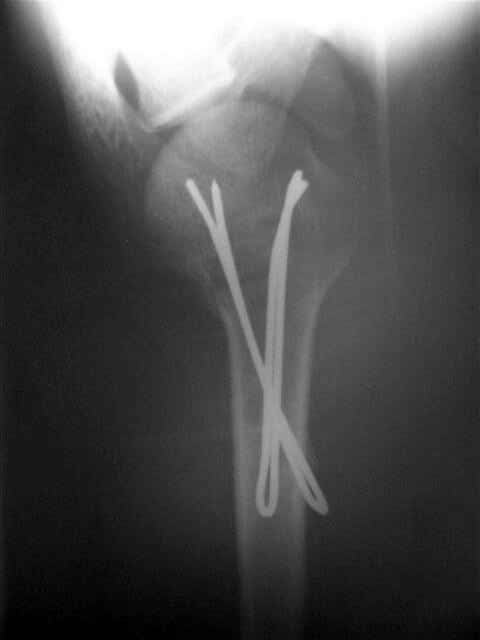

Здесь случай перелома-вывиха плеча, больному 56 лет, после "дважды" закрытой неудачной репозиции, опять же ургентно взяли в операционную, после полного общего обезболивания попытались сделать репозицию, и фиксацию провели спицами.

Больной находился в повязке, примерно напоминяющей косыночную, рекомендованы движения в локтевом суставе и маятниковые движения в плече, спицы удалены в три недели (были случаи миграции)

Больной амбулаторный, предупрежден на случай осложнения АВН головки.